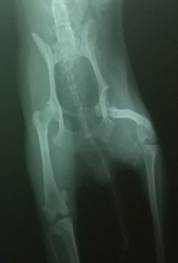

进行推拿后几小时,该犬就可以行走;2天后可以正常行走;1个月后完全恢复,正常活动。X线片显示髋关节已完全复位(见图2)。

图2:治疗前后髋关节X线照片